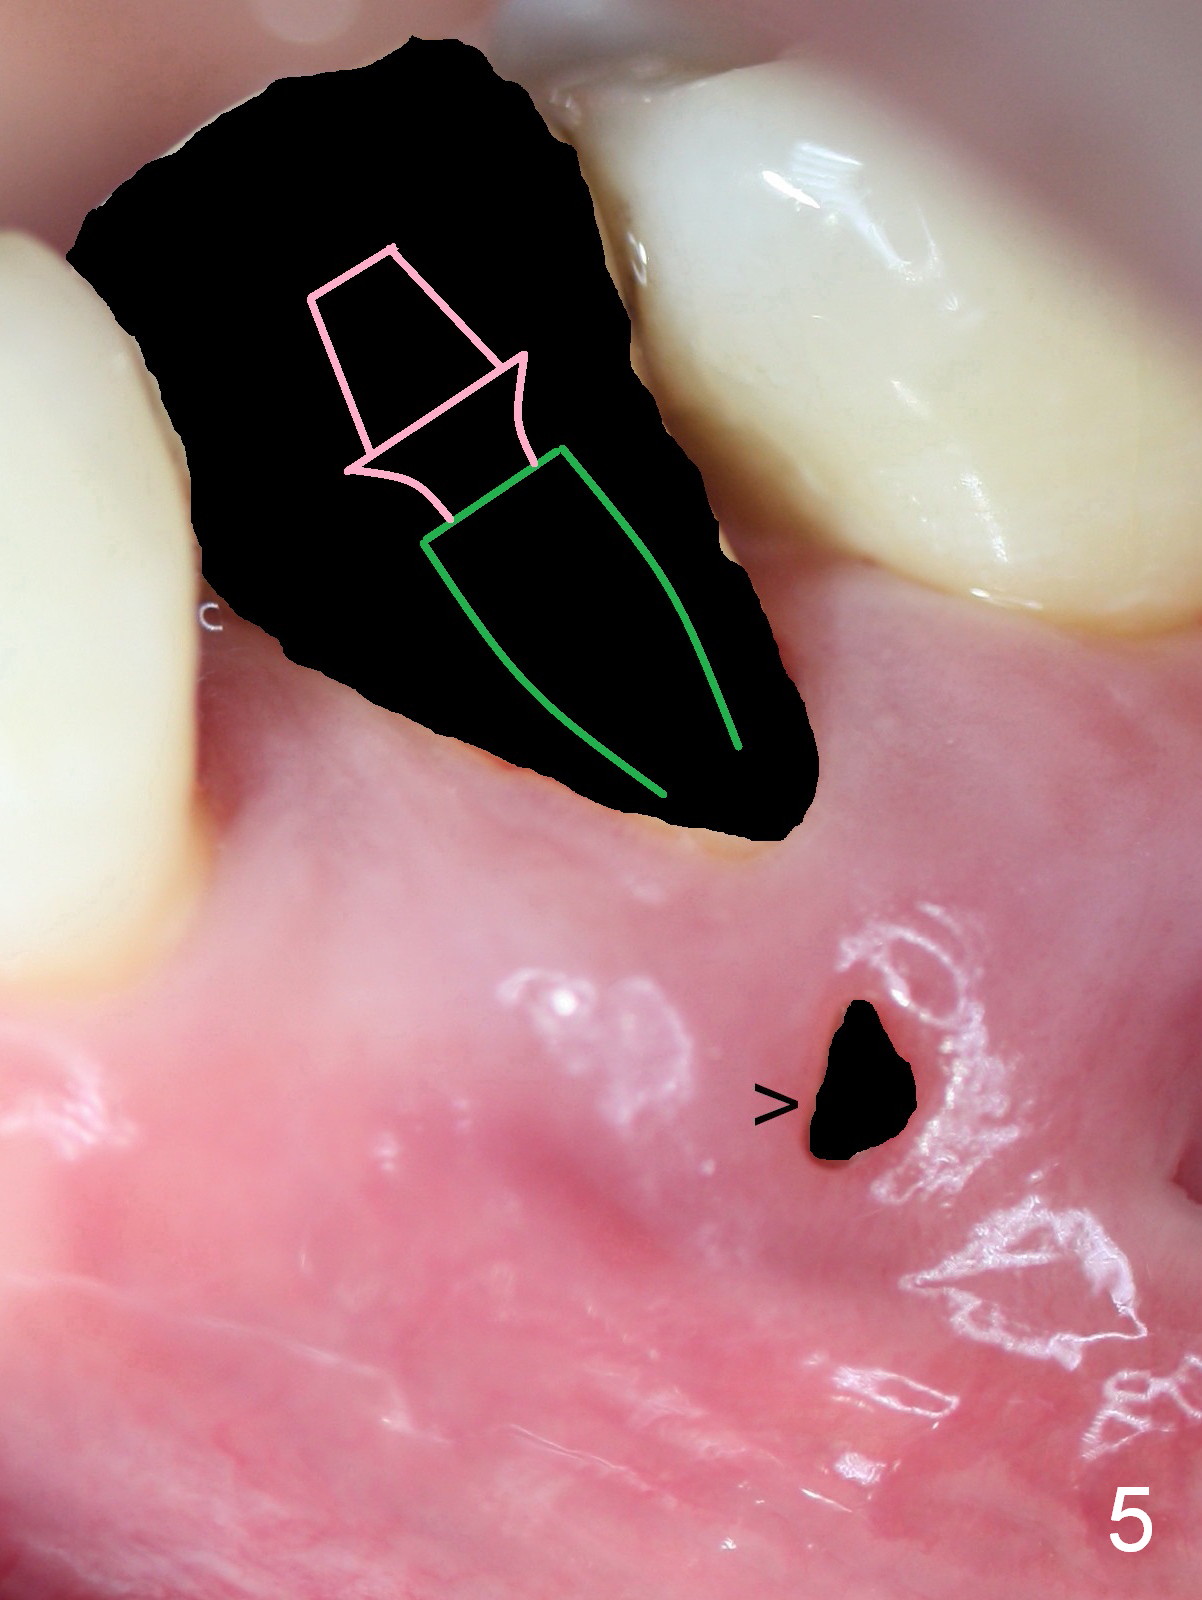

A 45-year-old man (JT) has endo failure at #20 with fenestration (Fig.1,2 black >) and fistula (white <). Insertion of a Gutta Percha at the fistula (Fig. 3 <; PA taken 2 years ago) indicates that the infection is dervied from the apex of the tooth #20. The socket will be soaked with 2% Xylo, 1:50,000 Epinephrine gauze. A 4.5x17 mm tissue-level (Fig.4) or 14 mm bone-level implant is placed as lingual as possible (Fig.5 green). If primary stability is achieved, an abutment is placed (pink). A large piece of resorbable membrane is used to cover the buccal defect (including buccal recession, fenestration and fistula (Fig.6 yellow dashed line). Two small pieces of non-resorbable membrane are placed to cover the gingival recession and the fenestration (Fig.7 white dashed line, buried underneath the edge of the gigniva). Then place bone graft buccally. Place a small piece of gauze (one layer) or plastic (from Tatum implant bag) over the 2nd membrane over the gingival recession and fabricate an immediate provisional. When the acrylic is partially set, remove the gauze or plastic from the provisional. After trimming and polishing, the provisional is cemented to securely keep the 2nd membrane in place. When the wound is healing and the 2nd membrane is stable, trim the buccal extension of the provisional. It is expected that the buccal hard and soft tissue will regenerate over the implant.